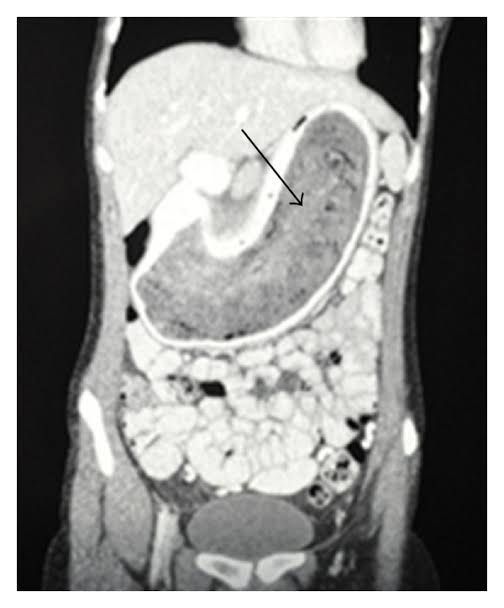

Trichobezoars (concretions of hair) are unusual and are usually found in young psychiatric females, who often deny eating their own hair (trichophagy). It is caused by the pathological ingestion of hair, which remains undigested in the stomach